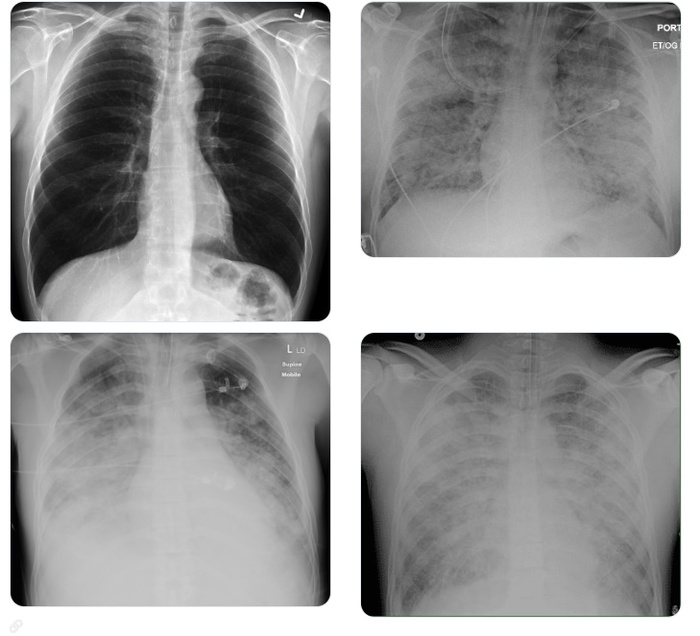

Итак,как выглядит ОРДС на снимке лёгких:

Первый снимок норма - остальные ОРДС